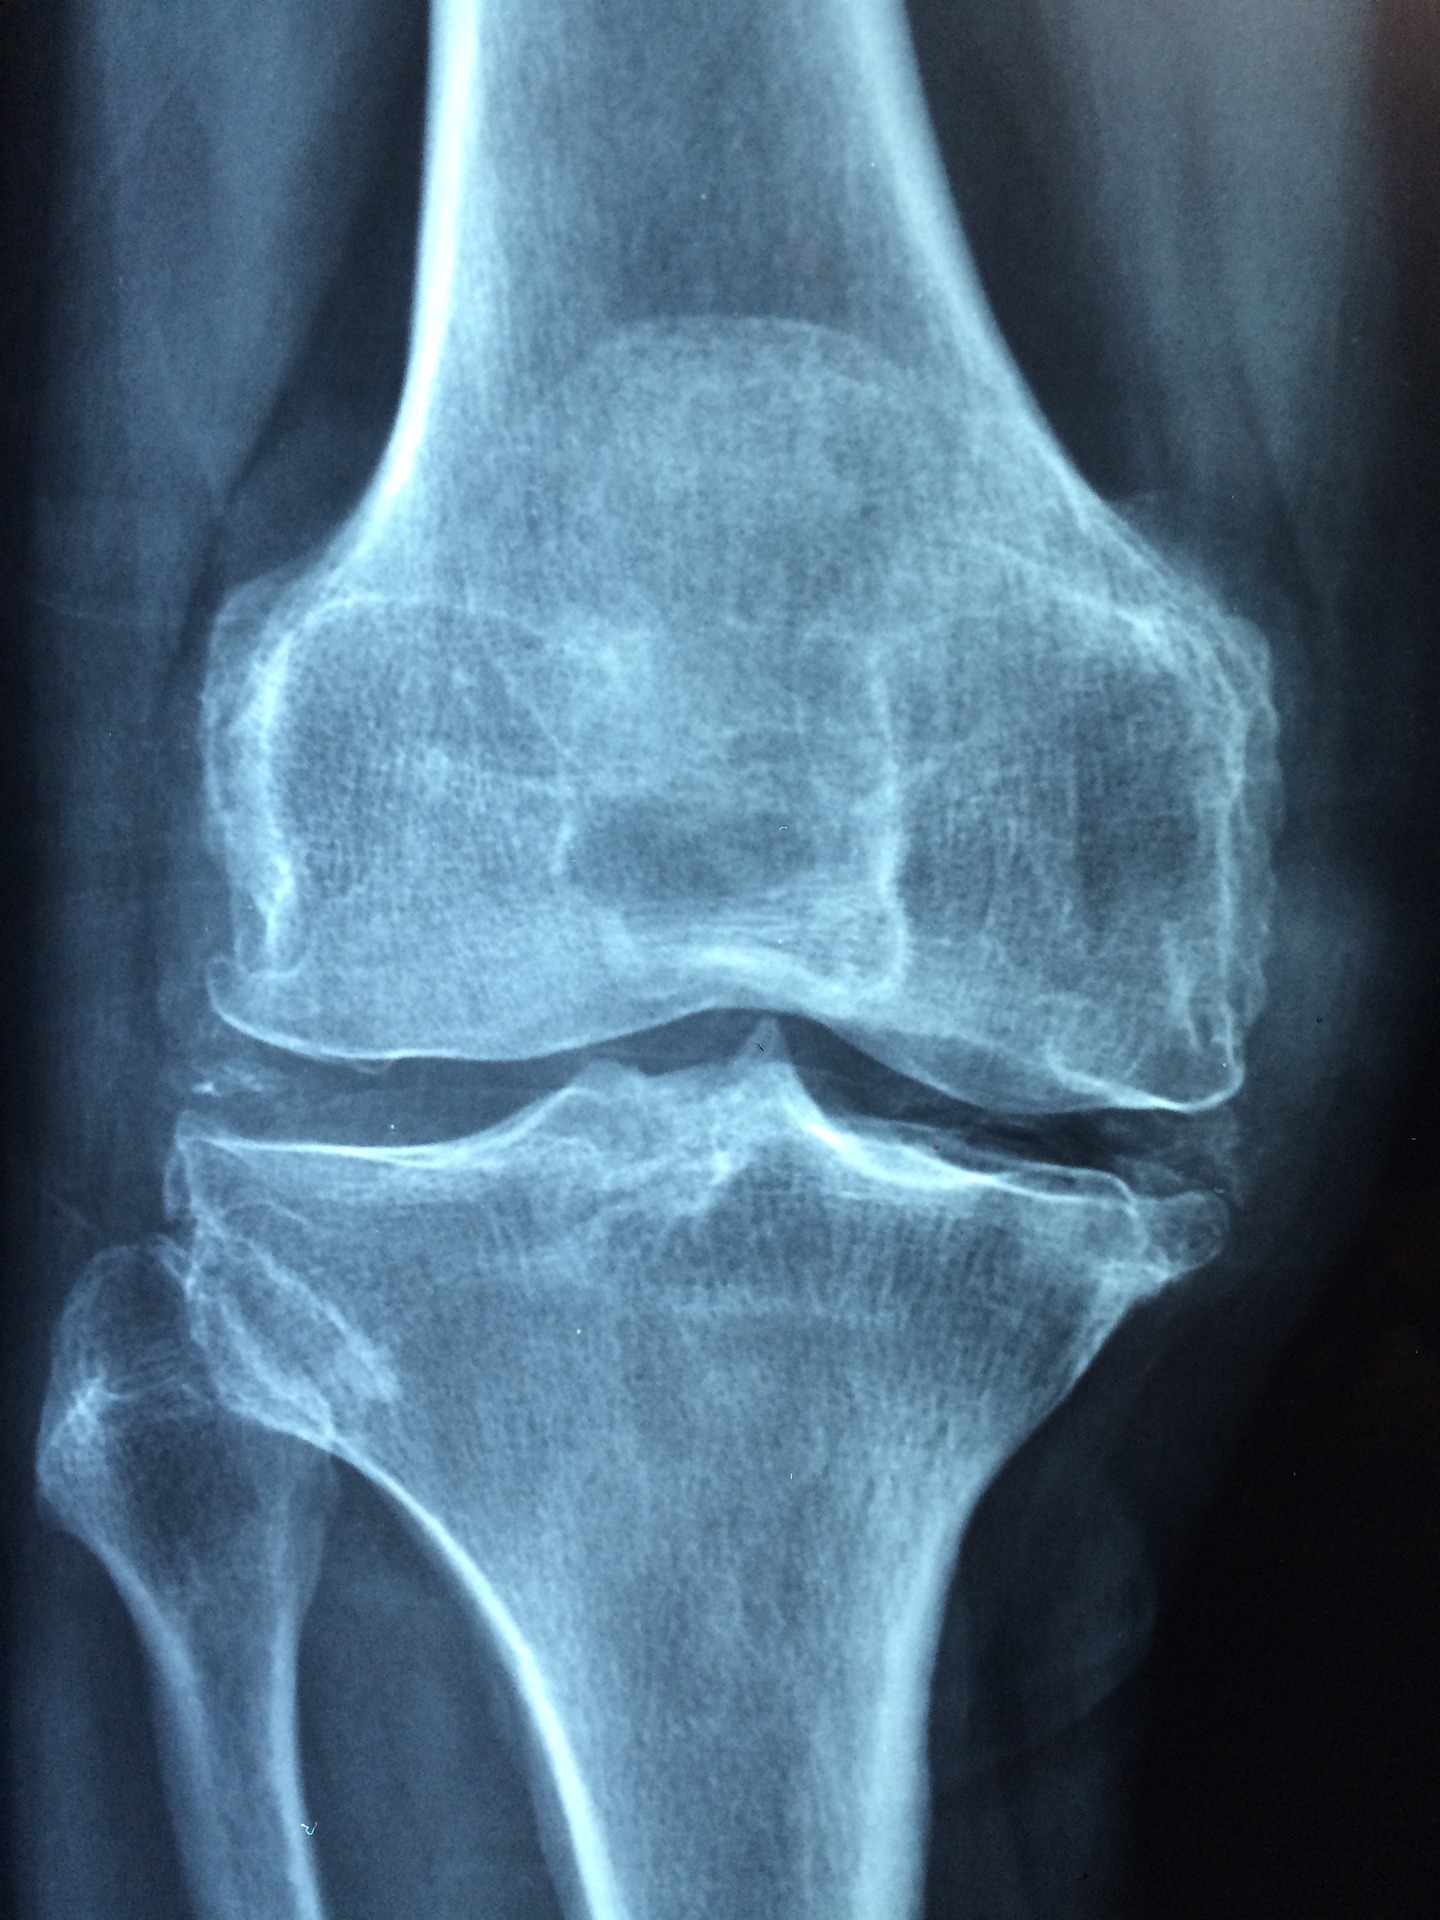

골다공증은 뼈의 밀도와 강도가 감소하여, 뼈가 더 쉽게 부러지거나 골절이 일어나는 상태입니다. 이 질환은 일반적으로 증상이 없어 진단이 지연되는 경우가 많으며, 일부 환자들은 통증이나 뼈의 변형이나 축소 등의 증상이 나타날 수 있습니다. 골다공증의 증상에는 다음과 같은 것들이 포함될 수 있습니다.

- 무릎, 엉덩이, 손목 등의 골절 : 뼈의 밀도가 감소하면 더 쉽게 부러질 수 있으며, 골다공증을 앓고 있는 환자들은 일반적으로 무릎, 엉덩이, 손목 등에서 더 많은 골절을 겪을 가능성이 높습니다.